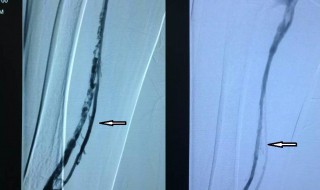

1、下肢血栓大多数是下肢血管的内膜受损和血流变慢造成的,一般情况下没有生命危险,如果下肢血栓脱落,可能会造成肺栓塞或者脑栓塞,就有生命危险。